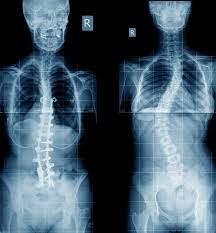

Kyphosis scoliosis / Occipito Cervical Fusion

Spine surgery for kyphosis is recommended for patients whose curvatures continue to progress or cause symptoms despite non-operative treatment. Corrective surgery for thoracic kyphosis is usually recommended when curves are larger than 80° to 90° when measured on x-rays. Kyphosis can extend into the mid or lower back and in those cases surgery is recommended for curves larger than 60° to 70° of kyphosis. Surgery is also an option for patients with disabling back pain or when kyphosis leads to compression of the spinal cord or nerves.

The goal of spinal reconstruction surgery is to decrease the patient's pain and to place the spine in a more natural position. Most commonly this surgery is performed through a posterior approach in the back of the spine. During the surgery, spinal implants including rods and screws are placed next to the spine. These implants correct the spinal deformity and stabilize the spine in its new position while the spine fuses, or mends, together. These bones ultimately heal into one solid piece for spinal stability and prevention of further curve progression. Complications may occur but are not common.

The majority of patients are satisfied with their pain relief and the results of their surgery. It is important that all patients are physically and psychologically prepared. All patients should stop smoking prior to any surgery, as smoking is extremely detrimental to your spine health, potential bone healing and successful surgical outcomes. Please review additional details with your surgeon prior to your surgery.